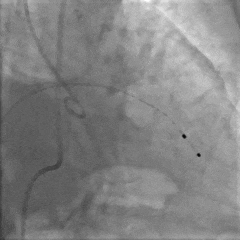

根部造影

导丝跨瓣